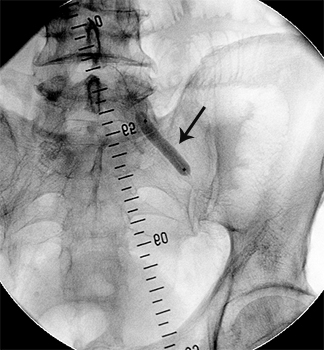

Приклади ангіограм:

стеноз правої ниркової артерії    пухлина підшлункової залози

Ниркова артерія (1), критичне звуження

ниркової артерії, (2) паренхіма нирки (3)